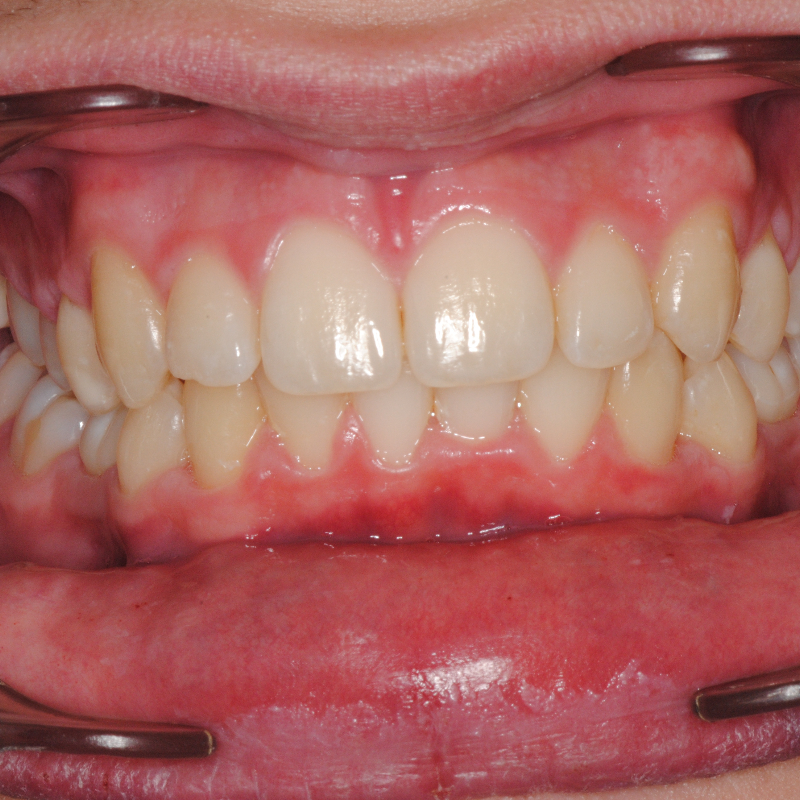

Prima e dopo trattamento con ortodonzia invisibile per l’allineamento dei denti